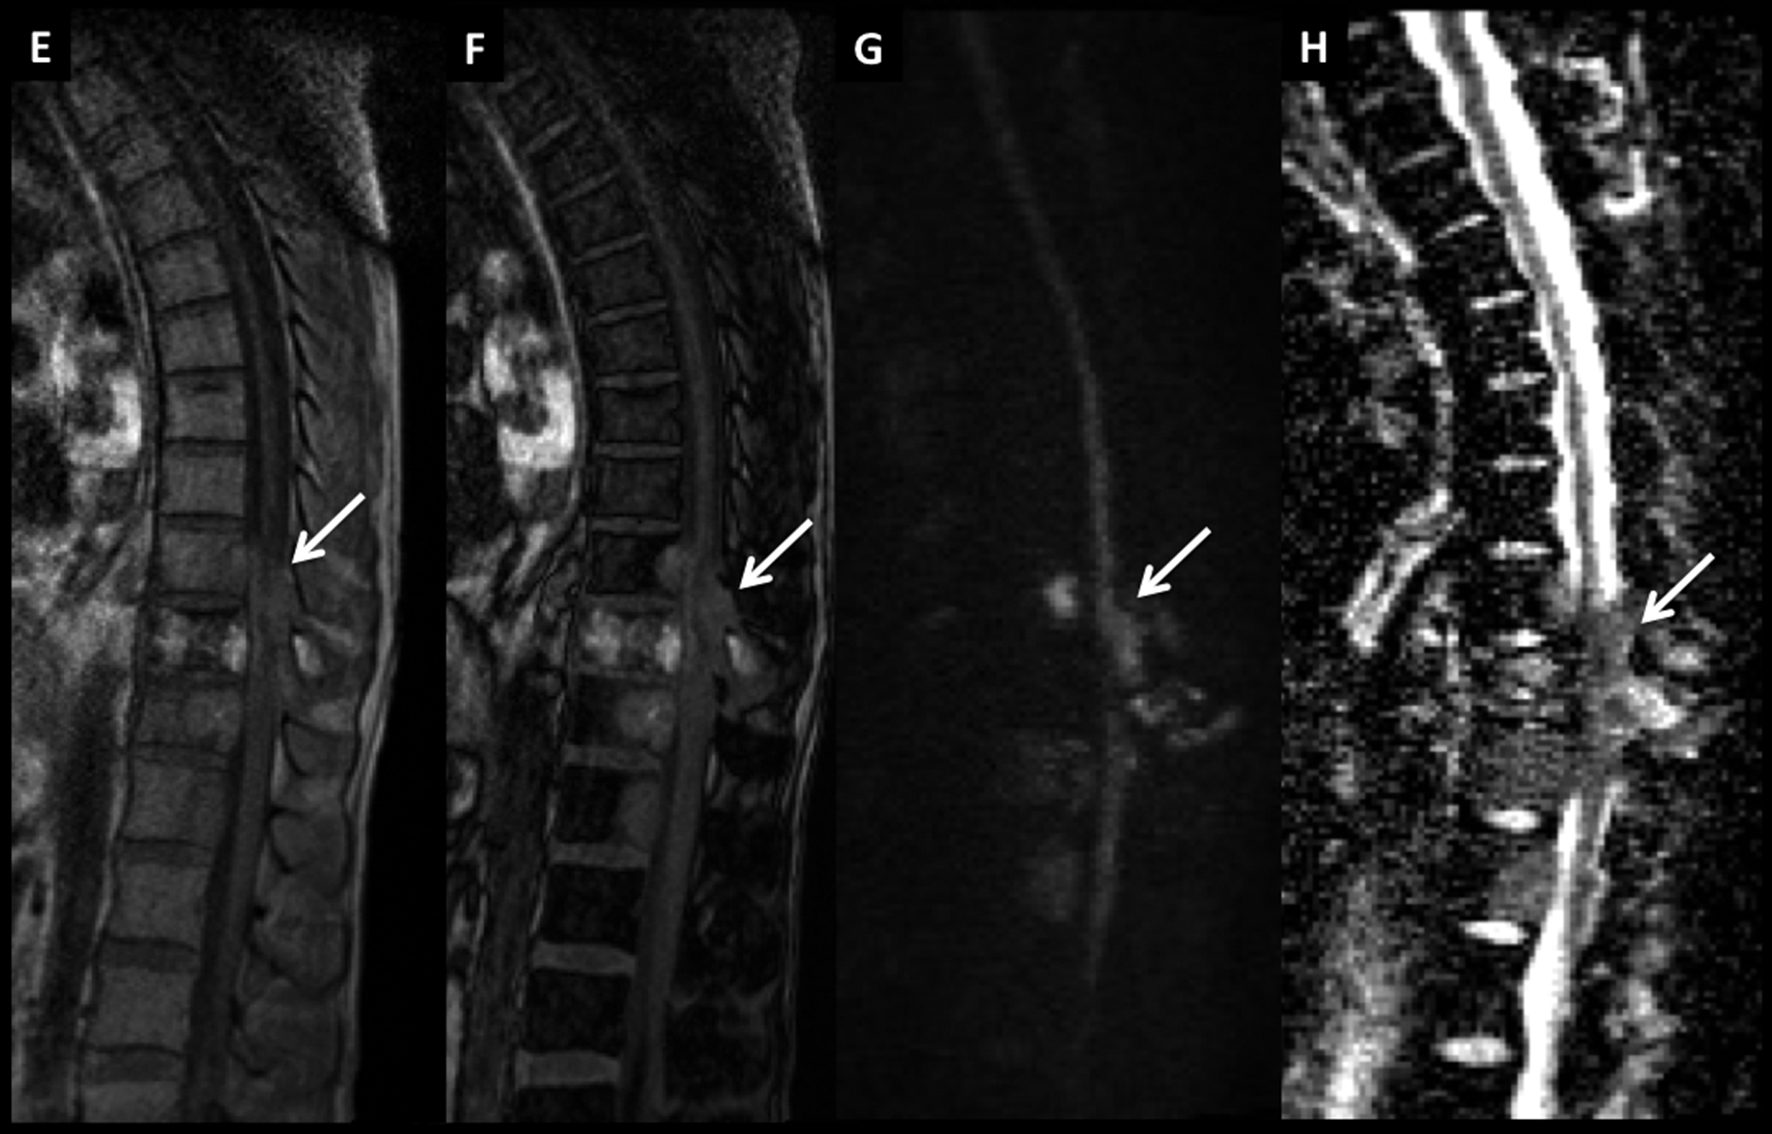

LNH, lesiones óseas múltiples y masa intrarraquídea extradural, compromiso secundario.

Paciente con diagnóstico de LNH sistémico y lesiones óseas múltiples (*) a nivel dorsal bajo y masa intrarraquídea extradural con compresión medular.

Las lesiones son de baja señal en T2 (A) y T1 (B) con edema óseo en STIR (C) y realce intenso, algo heterogéneo con el medio de contraste (D).

La masa intrarraquídea es sólida con intenso realce y que comprime el cordón medular. En secuencia T1 en fase (E) y fuera de fase (F) se observa el comportamiento habitual de las lesiones agresivas, con aumento de señal en el pasaje de una fase a la otra. En difusión b1000 (G) y mapa de ADC (H) las lesiones son de alta y baja señal respectivamente, un elemento habitual en lesiones agresivas.